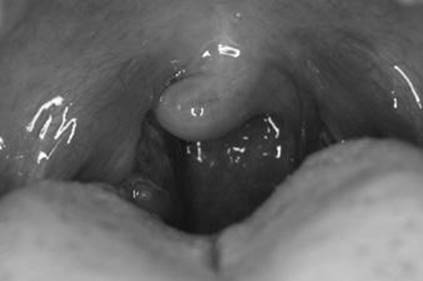

Streptococcal pharyngitis (> 2 years) (see Figure 12-3):

FIGURE 12-3. Streptococcal pharyngitis.

Note white exudates on top of erythematous swollen tonsils.